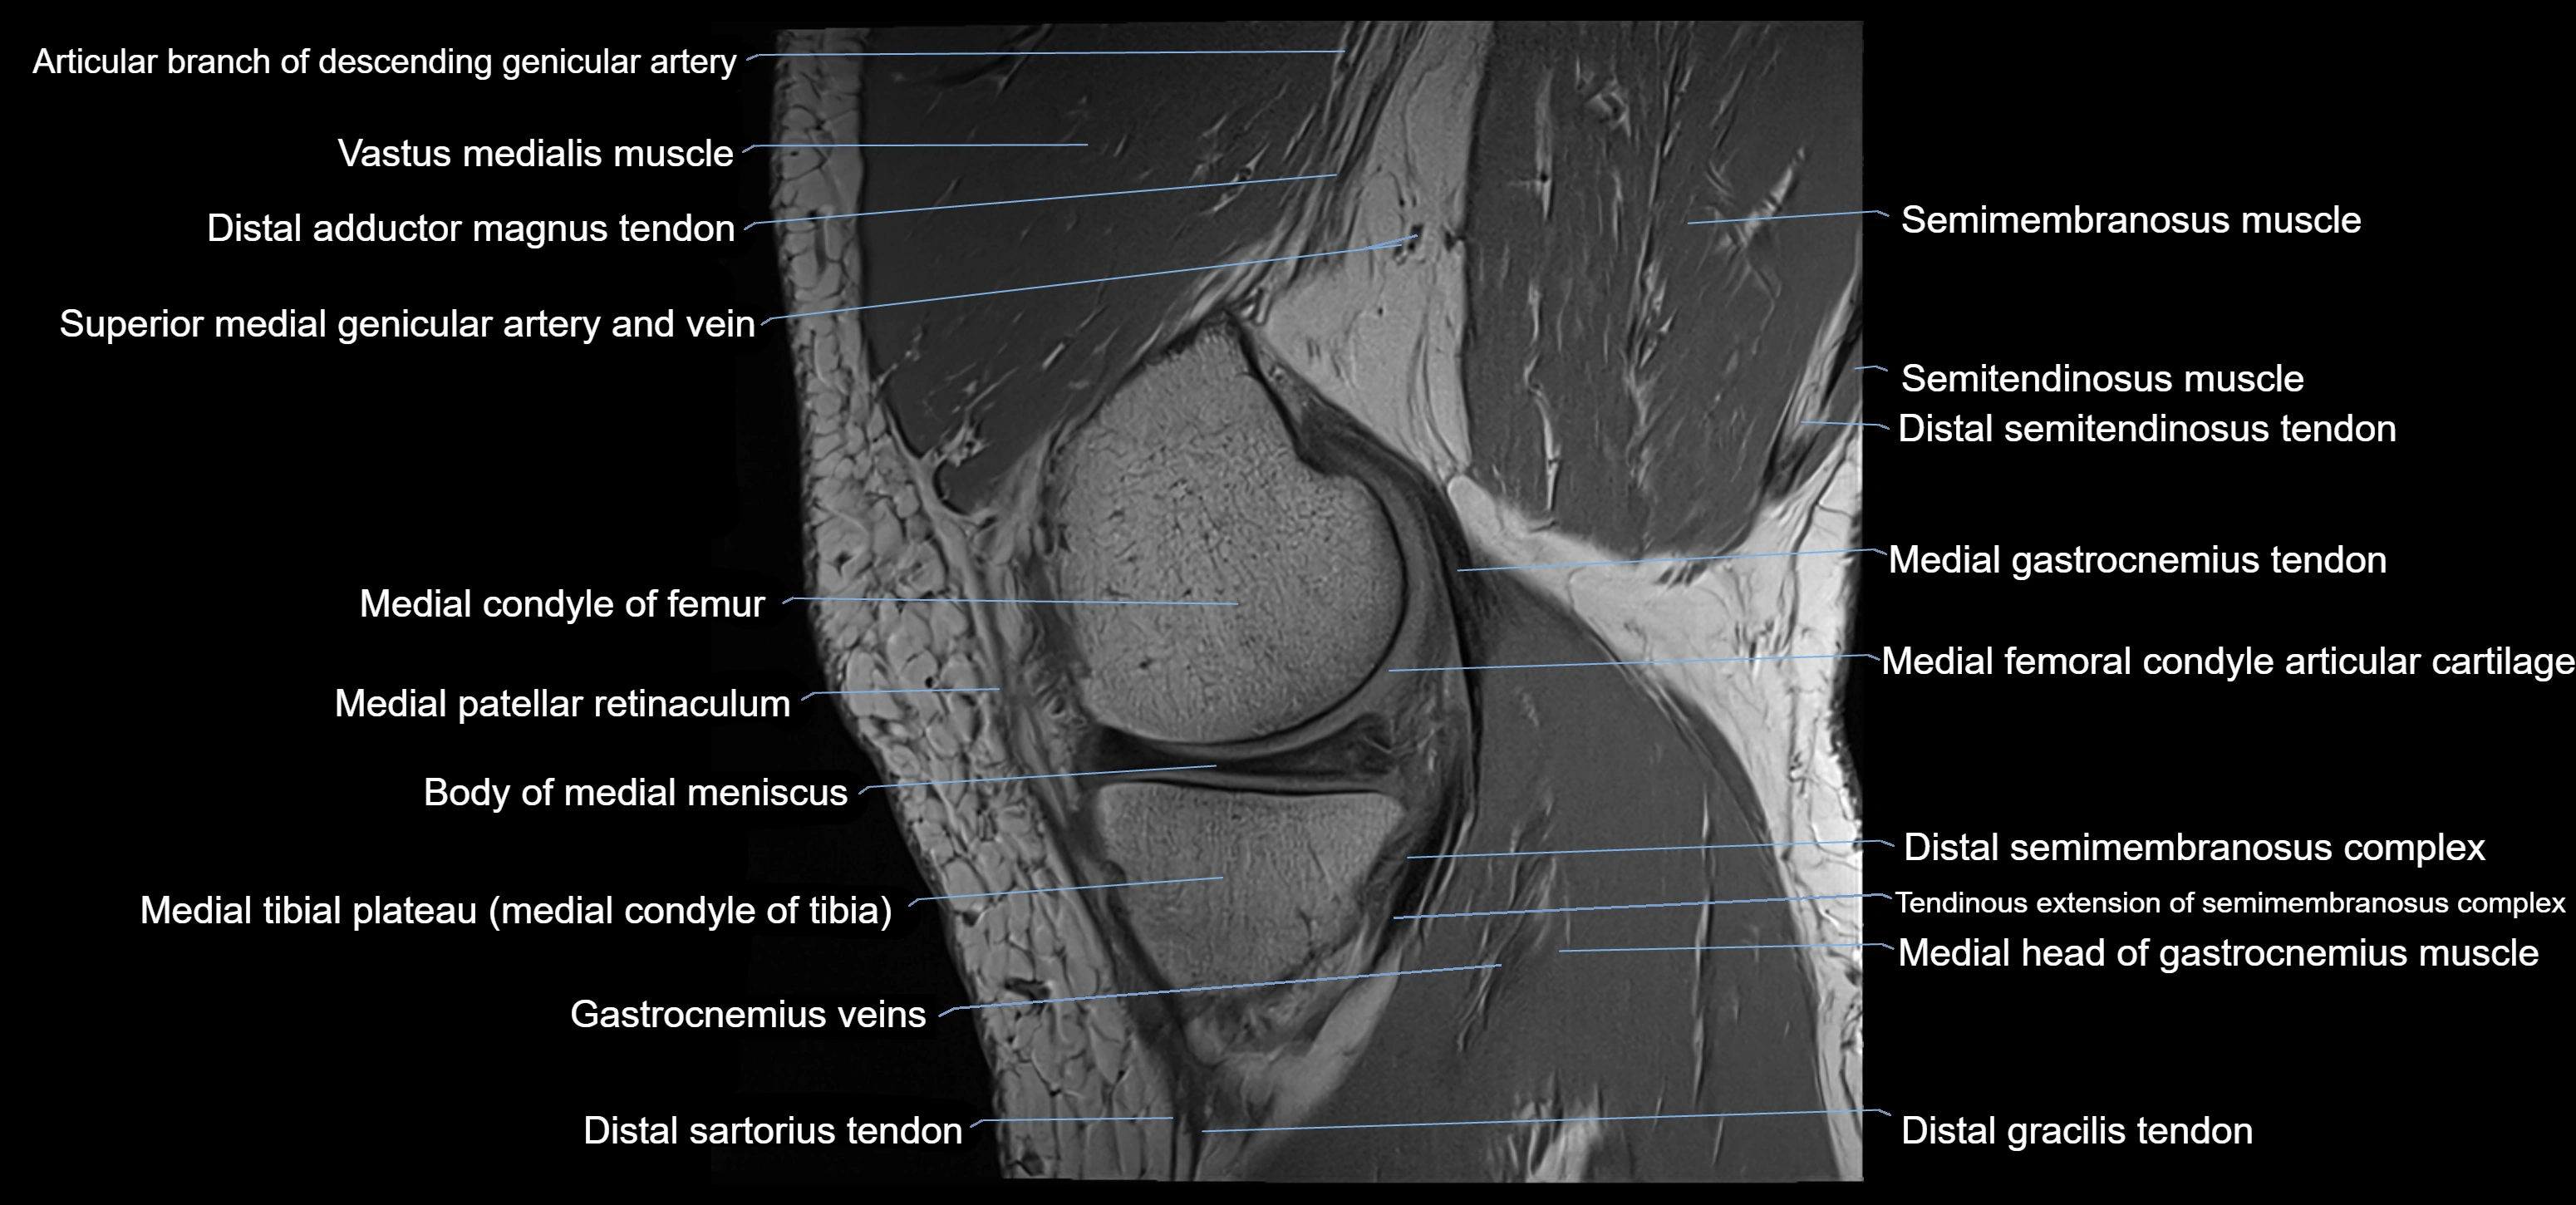

- Distal adductor magnus tendon

- Distal semimembranosus tendon

- Body of medial meniscus

- Medial condyle of femur

- Medial gastrocnemius tendon

- Medial head of gastrocnemius muscle

- Medial patellar retinaculum

- Medial tibial plateau

- Sartorius muscle

- Sartorius tendon (Distal)

- Semimembranosus muscle

- Semitendinosus muscle

- Superior medial genicular artery

- Superior medial genicular vein

- Vastus medialis muscle